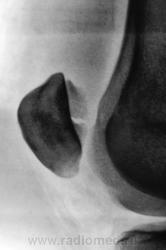

перелом надколенника( редко такой встречается) препателярная гемабурса, гемартроз, сильно пострадала суставная поверхность надколенника

Наверно все таки пателля бипартита. Представить, чтобы так красиво и ровно откололось - трудно... А мягкотканный компонент знатный...

Сам думал о "бипарцита", кстати, недавно был случай с "трипарцита". Но в данном случае был в растерянности, клиника "зашкаливает", конечно, возможно из-за мягкотканного компонента.

Кстати, на обычной рентгенограмме, произведенной в ургентных условиях "мягкотканный компонент" едва угадывается. Сильно "Сиар" спасает.

В минус травме говорит такая "красивенькая форма" отломка? НО при бипарите про мягкотканный компонент я данных ненашел..